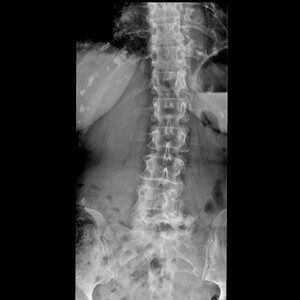

Praxisnahe Röntgenfälle, strukturierte Befundung, fundiertes Fachwissen. Lernen, üben, anwenden — mit echten Fällen aus der klinischen Praxis.

Die spezialisierte Lernplattform für Projektionsradiographie. Im Mitgliederbereich steht eine stetig wachsende Fallsammlung mit realen Röntgenbildern zur Verfügung — systematisch aufgebaut, mit strukturierter Befundung, Befundcheck und klinisch relevanten Zusatzhinweisen.